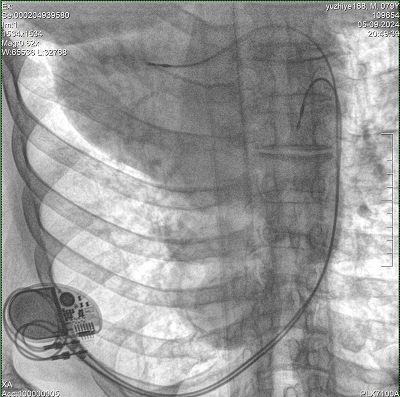

具备血管造影及数字减影(DSA)、路径图(Road-map)、透视、摄影等功能。 广泛适用于介入科、血管外科、肿瘤科、消化内科及骨科等多个临床科室,典型应用包括:TACE(肝肿瘤栓塞与化疗灌注术)、心脏起搏器置入术、四肢动脉造影术、下肢静脉滤器置入术、ERCP(经内镜逆行胰胆管造影术)等。

核心DSA软件可实时生成高清血管影像,结合路径图功能,在手术中为医生提供血管导航。

设备搭载自主研发的大功率高压发生器、高热容球管与大尺寸平板探测器,配合先进图像处理算法及高效冷却循环系统,能够在长时间手术过程中持续输出高清图像并保持帧率稳定。

预留高压注射器联动接口,C形臂开始透视时,高压注射器自动注入造影剂,提高术中造影减影效率,减少医师手推造影剂所受到的辐射暴露剂量。